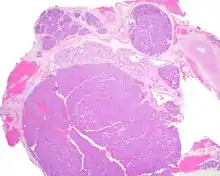

Most patients present in the 7th decade of life, with females affected much more commonly than males (about a 4:1 ratio). The vast majority of the tumors present in the upper lip, although a few present in the palate or buccal (cheek) tissue as a slowly enlarging mass.[3] It is curious that the tumor may show multifocality or multinodularity, a finding that should not be confused with invasion clinically or with malignancy.[1][4]

Tumors are usually small because they come to clinical attention early on in development, with an average size of about 1.6 cm.[1] There is a very characteristic appearance to the tumor when reviewed histologically.

There are often small luminal squamous balls or morules. There is a very well developed supporting tissue that is a loose, fibrillar stroma, rich in hyaluronic acid and chondroitin sulphate.[1] In a few cases small calcifications or microliths may be present. Although seldom necessary, a pathologist can do immunohistochemistry studies to confirm the diagnosis, with the cells strongly reactive with pancytokeratin, S100 protein and SOX10, with a delicate GFAP reaction around the periphery.[5][1][6][7] Even though it is a benign tumor, it must be separated from a basal cell adenoma, pleomorphic adenoma, adenoid cystic carcinoma, and polymorphous adenocarcinoma.